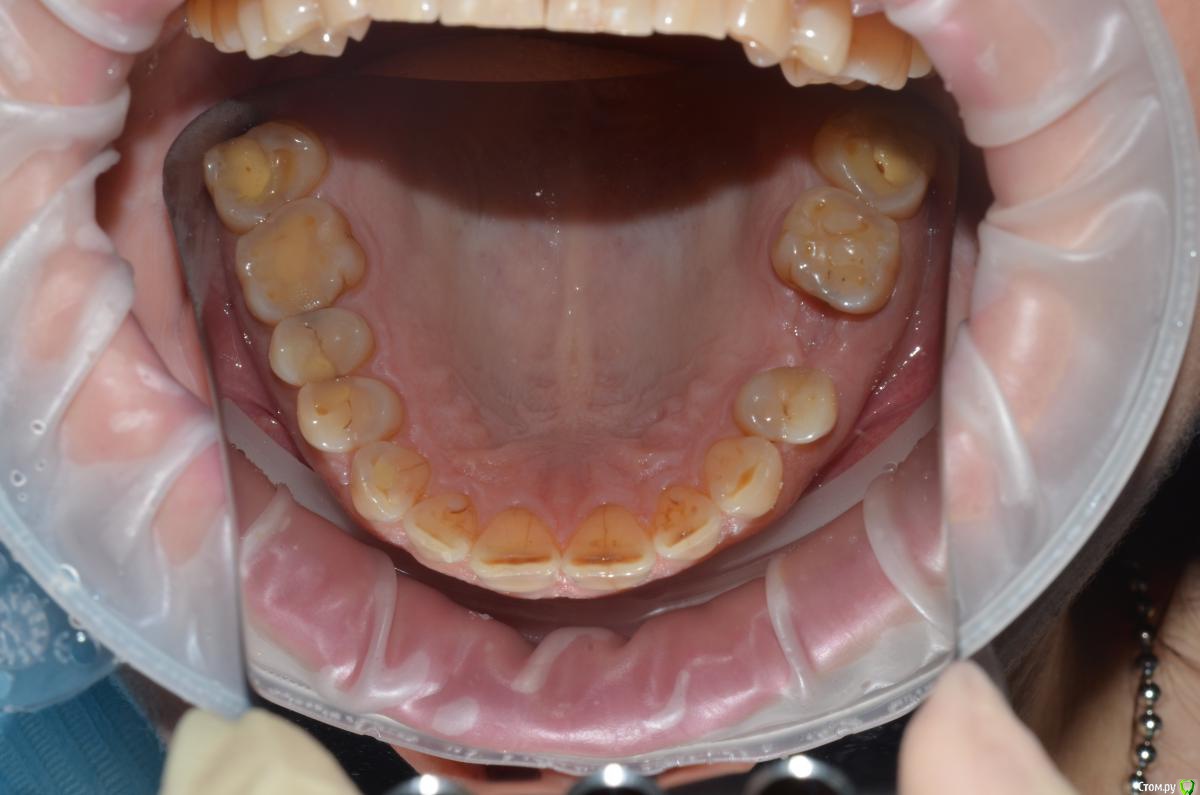

CHEREDNICHENCO Опубликовано 12 сентября, 2015 Поделиться Опубликовано 12 сентября, 2015 До протезирования, без смещения! 1.5, 1.6 кариес II класс, 4.3 - V. Как сагиттальную окклюзионную кривую выводили??? Не проще было подождать подхода аббатов...со времянками? Ссылка на комментарий

NazranDantist Опубликовано 12 сентября, 2015 Автор Поделиться Опубликовано 12 сентября, 2015 (изменено) До протезирования, без смещения! 1.5, 1.6 кариес II класс, 4.3 - V. Как сагиттальную окклюзионную кривую выводили??? Не проще было подождать подхода аббатов...со времянками?Кариеса нет.Смещение есть Изменено 12 сентября, 2015 пользователем NazranDantist Ссылка на комментарий